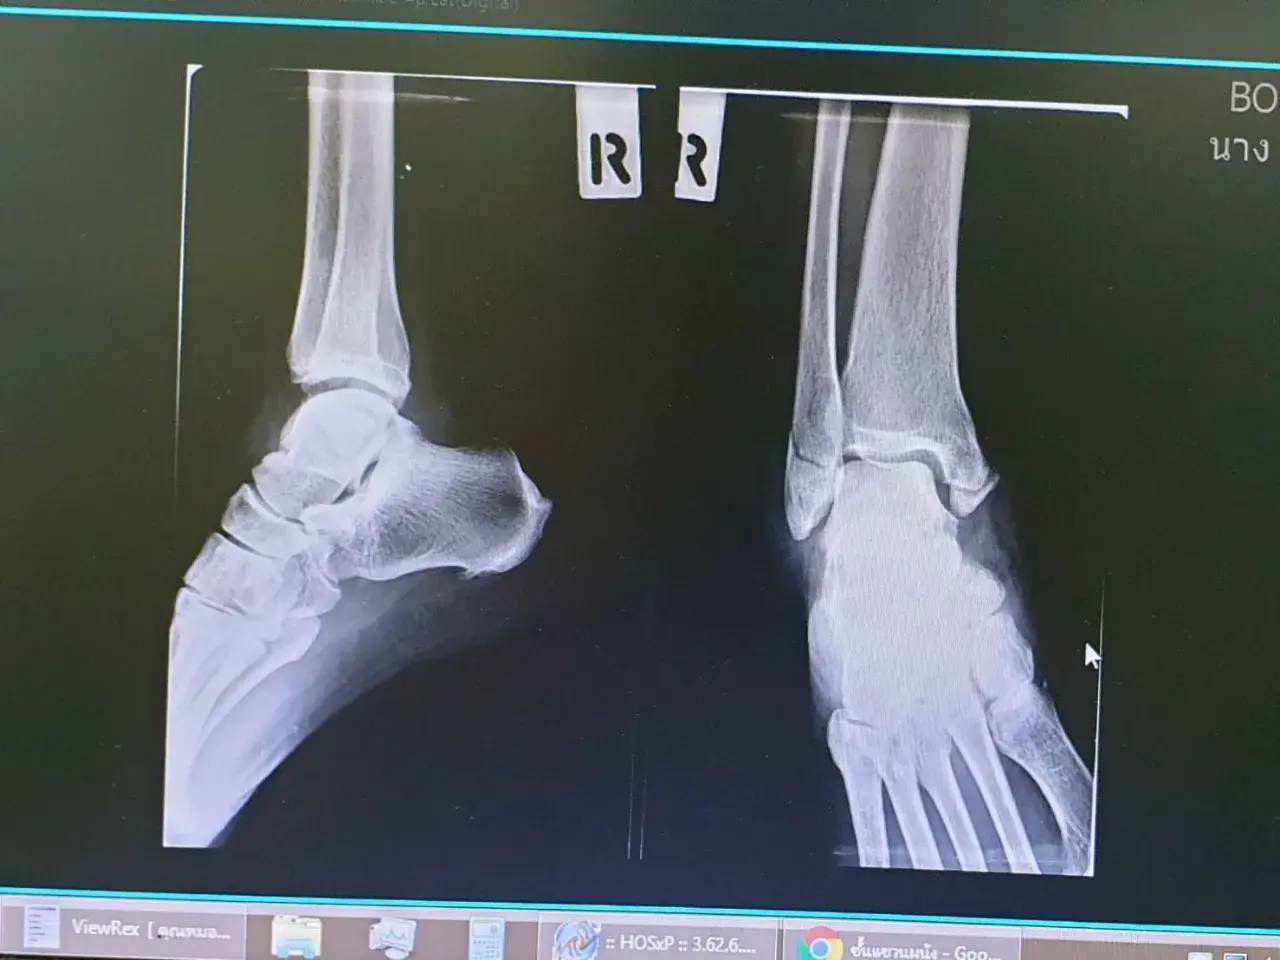

การผ่าตัดใส่เหล็กดามกระดูก หรือที่หลายคนเรียกว่า "ใส่เหล็ก" เป็นวิธีการรักษาเวลาที่กระดูกหักรุนแรง หรือกระดูกหักแล้วไม่สามารถติดกันเองได้ตามปกติ หมอจะใช้เหล็กหรือวัสดุพิเศษมายึดกระดูกให้เข้าที่ เพื่อให้กระดูกเชื่อมติดกันได้เร็วและแข็งแรงขึ้น

เวลาใส่เข้าไป หมอจะผ่าตัดเปิดผิวหนังไปถึงกระดูก แล้วใช้เหล็ก (อาจเป็นแผ่น หรือแท่งยาว ๆ) ยึดกับกระดูกด้วยน็อตหรือตะปูเฉพาะทาง เสร็จแล้วเย็บปิดแผล